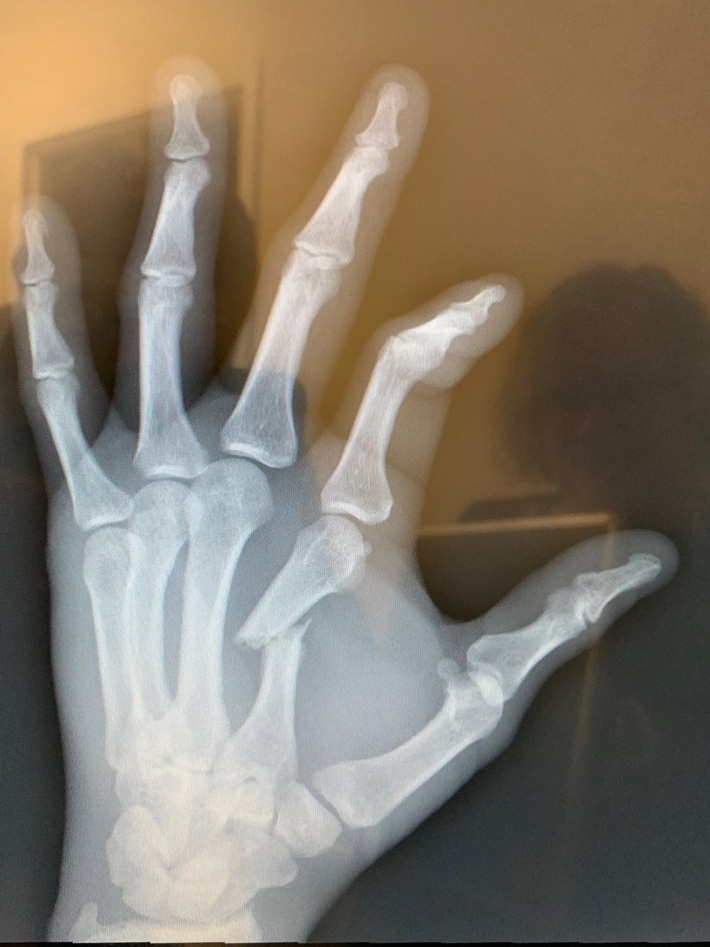

Thắng lợi của Anthony Smith còn đáng chú ý hơn khi anh đã cắn răng thi đấu dù tay trái đã bị gãy ở hiệp thứ 2.

Gustafsson vẫn trung thành với chiến thuật này trong hiệp 2. Tuy vậy, võ sĩ chủ nhà vẫn dính không ít đòn tay của đối thủ và tỏ ra thấm mệt. Dù vô tình bị gãy tay trong một pha tấn công, Smith vẫn không dừng lại và liên tục trút mưa đòn về phía đối diện.

Dù gãy tay, võ sĩ người mỹ vẫn hạ gục đối thủ của mình